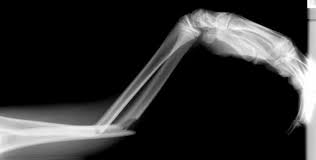

→ Fracturas: Pérdida de la continuidad de los huesos.

- Anatomía radiológica: Permite aplicar los conocimientos anatómicos al interpretar imágenes radiográficas de estructuras normales del cuerpo humano. Hay que tener en cuenta el tipo de estudio y la región y posición estudiada.